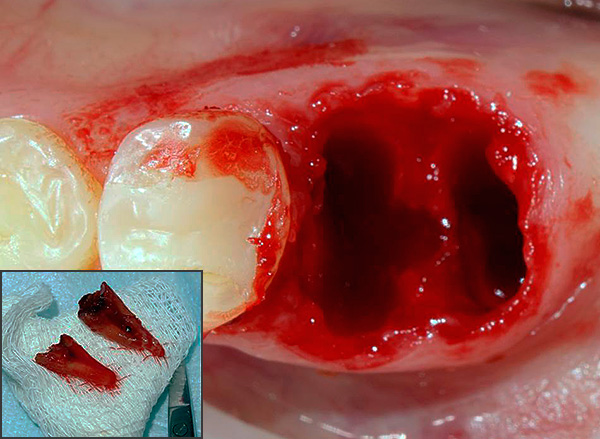

- Con fratture complesse del dente (ad esempio, con una longitudinale - vedi l'esempio nella foto sotto);

Foto di un dente le cui radici sono separate da un trapano prima della rimozione: